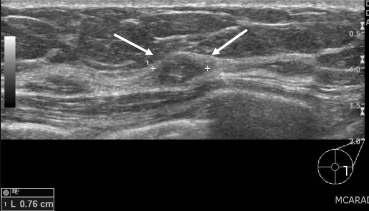

Figuur 8

Echografische afbeelding van een scherp begrensde, ovale, parallelle massa in het mediale bovenkwadrant van de rechtermamma, passend bij een fibroadenoom. Ten tijde van het eerste onderzoek wordt hiervoor een BI-RADS 3 afgegeven. Als de massa na zes maanden onveranderd is gebleven, dan wordt de classificatie een BI-RADS 2 en is verdere controle niet meer nodig.